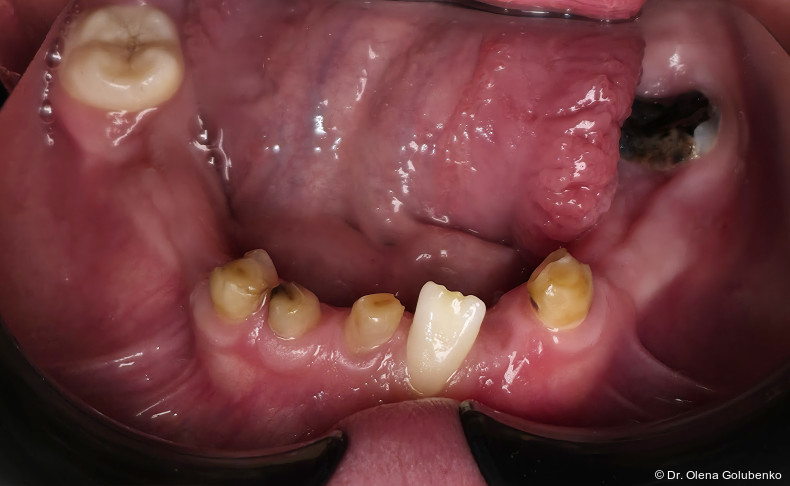

Das dentale Erscheinungsbild ist häufig sehr charakteristisch und erlaubt bereits früh einen Syndromverdacht. Typische Befunde sind:

• lang anhaltende Persistenz der Milchzähne

• ausgeprägte Retention der bleibenden Zähne

• multiple überzählige Zähne

• fehlende oder stark verzögerte spontane Zahndurchbrüche

• Engstände und Fehlstellungen

Die dreidimensionale Bildgebung zeigt meist eine hohe Anzahl nicht durchgebrochener permanenter und überzähliger Zähne, die in unterschiedlicher Lage im Kiefer verbleiben (Abb. 3+4).